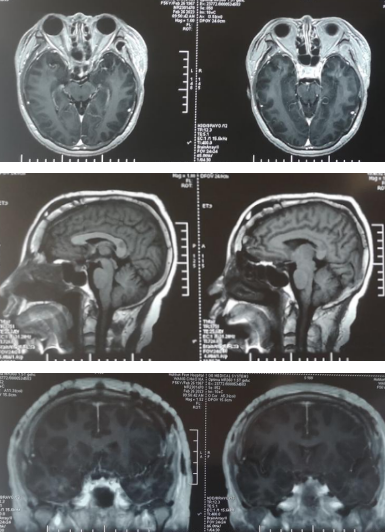

术后复查:头颅核磁

手术过程:麻醉医生贺林春精心细致地为患者实施气管插管全麻,BIS和鼻温监测,以及中心静脉置管,为手术提供安全保障;在贾群英护士长,手术护士乌日罕、樊荣的默契配合下,手术顺利进行,术中见肿瘤基地位于鞍结节,前方向蝶骨平台区生长,两侧包绕颈内动脉及双侧视神经,并向视神经管内生长,后方压迫垂体及垂体柄,向上向后推挤视交叉及三脑室底部,肿瘤色粉红,质地软韧,血供丰富,与视神经粘连严重,显微镜下分块切除肿瘤。术后病理回报砂粒体型脑膜瘤(WHO I)。术后患者视力、视野明显好转,复查头颅核磁肿瘤切除干净。

术后眼科检查:双眼视力OS:0.4,OD:0.1 双眼未见视野缺损。